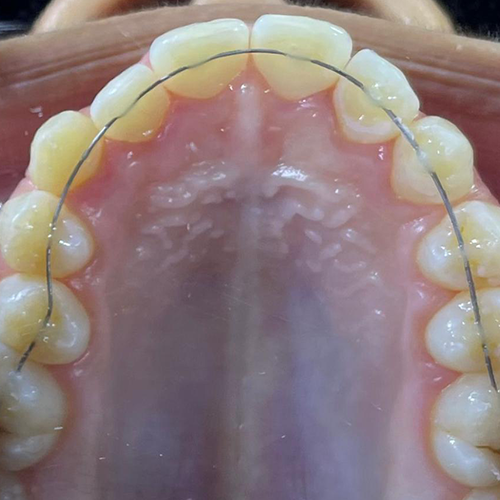

Comprueba en la práctica cómo el conocimiento se transforma en resultados reales a través de los casos de nuestros alumnos.

SALA DE PROCEDIMIENTOS

Siga clases prácticas y la evolución de casos clínicos reales directamente desde la clínica del Dr. Ary Nunes.